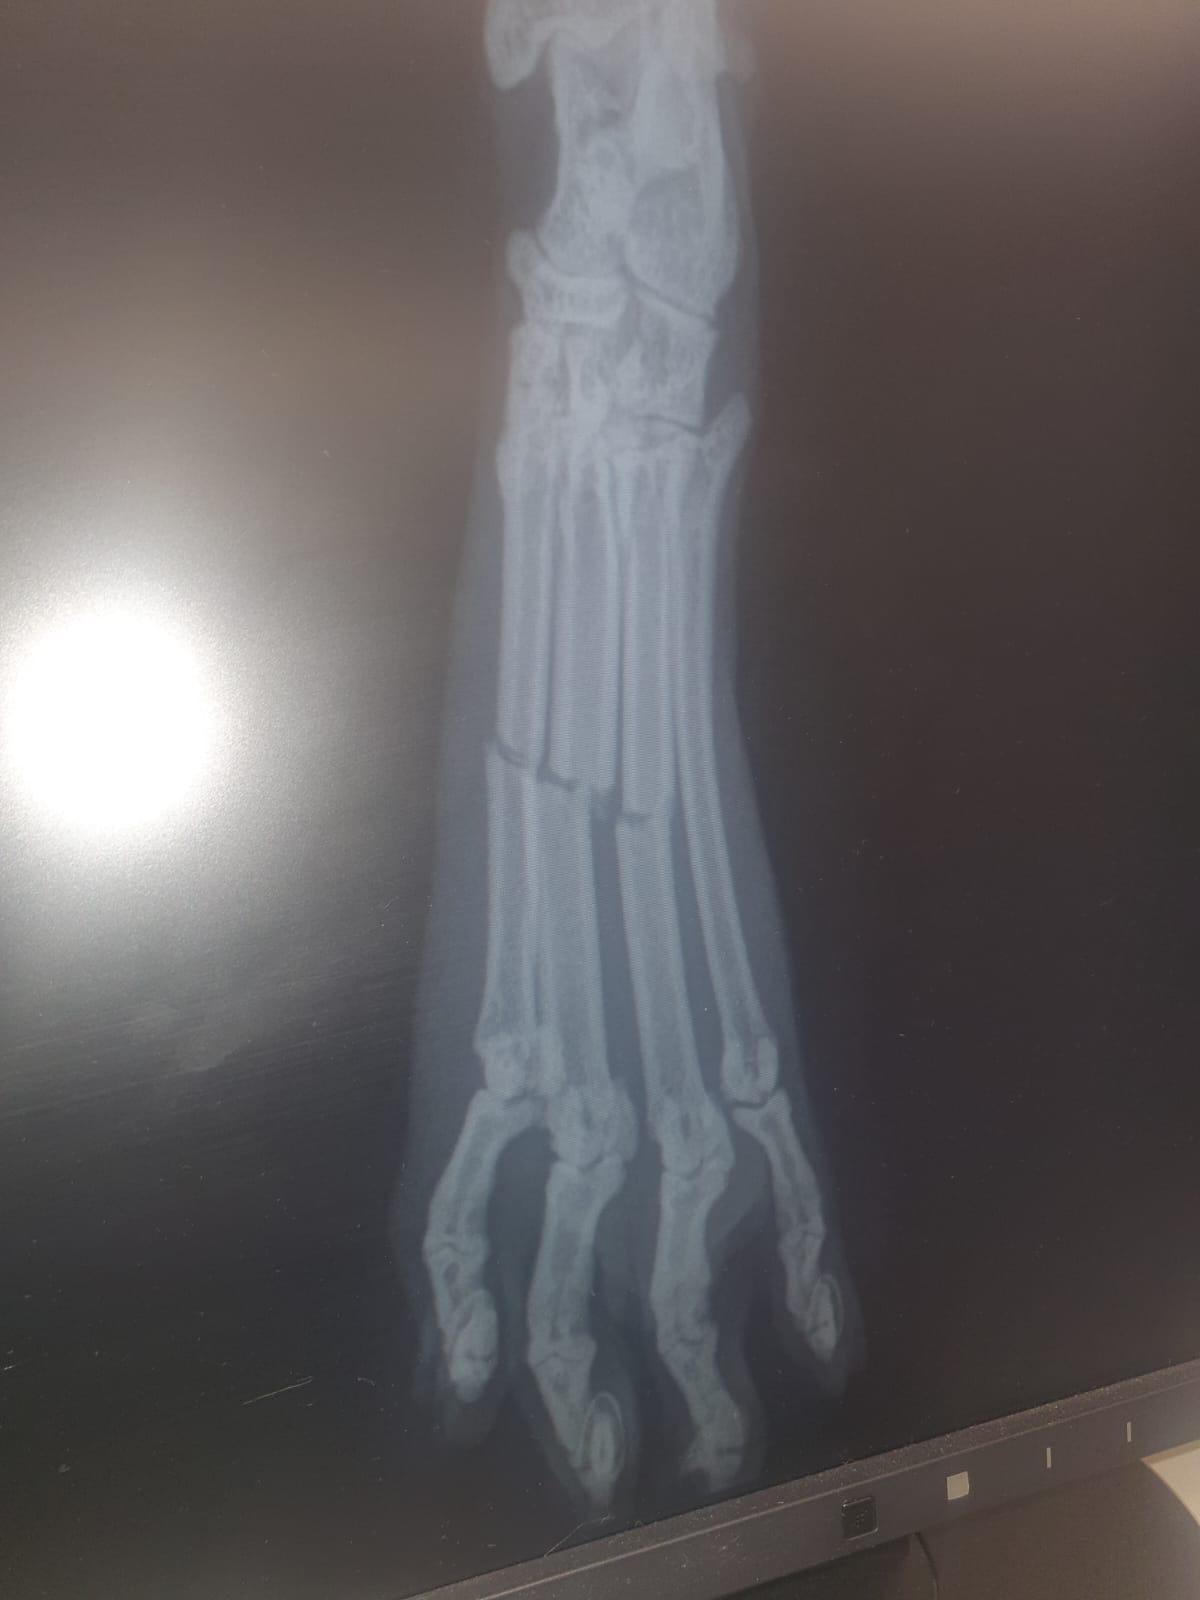

This morning, Zokni gave us a terrible scare by jumping from an upstairs window. Thankfully, we found him quickly—frightened and hiding in the front garden. A visit to the vet and some x-rays confirmed our fears: Zokni has three fractures in his foot. Sadly, the type of injury he has will likely require surgery and metal pins to heal properly, with a total cost estimated at £2,700.

Our pet insurance will only cover £1,000, and we’re now facing a difficult decision. There is a more conservative, non-surgical option involving splints, bandages, and regular check-ups, which would allow Zokni to come home and recover gradually. This treatment would still cost up to £1000. However, surgery offers the best chance for a full recovery—and we would love to give him that chance.

Zokni needed to have another sedation and re bandage his leg, as he took the first bandage off. Next week check up again, for repeat x ray. The vet team is positive with his progress for now, he wont have the micro-pin -surgery. Your kind donation goes a long way to the bills, and we are very grateful xxx